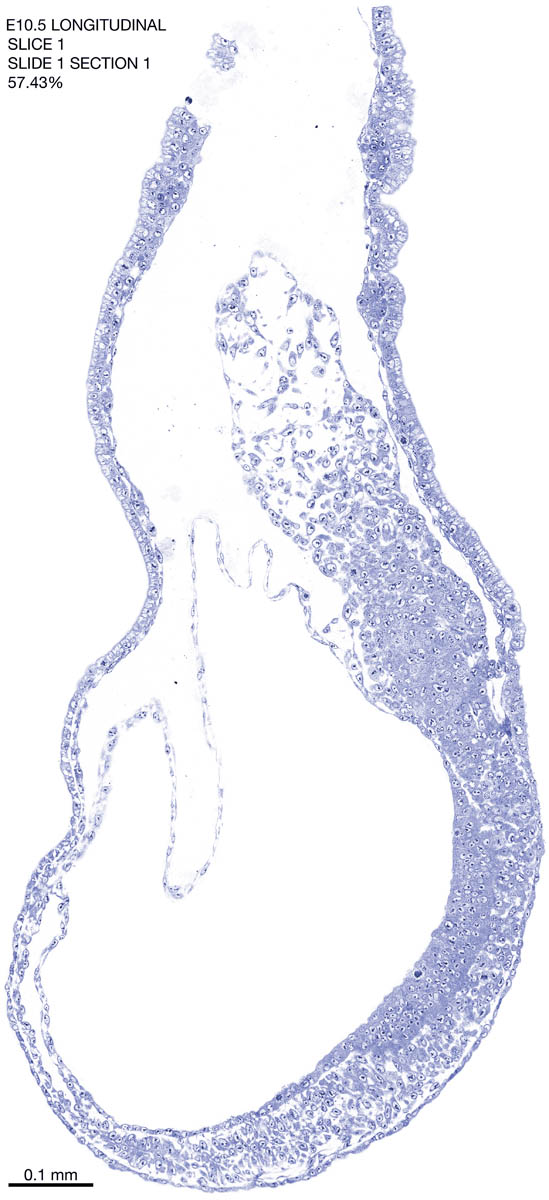

E10.5 Longitudianal Archive This page contains jpg files of ALL SLICES (each 3µm thick) that were scanned of the E10.5 longitudinally cut specimen. Download: Large | High Res Download: Large | High Res Download: Large | High Res Download: Large | High Res Download: Large | High Res Download: Large | High Res Download: Large | High Res Download: Large | High Res Download: Large | High Res Download: Large | High Res Download: Large | High Res Download: Large | High Res Download: Large | High Res Download: Large | High Res Download: Large | High Res Download: Large | High Res Download: Large | High Res Download: Large | High Res Download: Large | High Res Download: Large | High Res Download: Large | High Res Download: Large | High Res Download: Large | High Res Download: Large | High Res Download: Large | High Res Download: Large | High Res Download: Large | High Res Download: Large | High Res Download: Large | High Res Download: Large | High Res Download: Large | High Res Download: Large | High Res Download: Large | High Res Download: Large | High Res Download: Large | High Res Download: Large | High Res Download: Large | High Res Download: Large | High Res Download: Large | High Res Download: Large | High Res Download: Large | High Res Download: Large | High Res Download: Large | High Res Download: Large | High Res Download: Large | High Res Download: Large | High Res Download: Large | High Res Download: Large | High Res Download: Large | High Res Download: Large | High Res Download: Large | High Res Download: Large | High Res Download: Large | High Res Download: Large | High Res Download: Large | High Res Download: Large | High Res Download: Large | High Res Download: Large | High Res